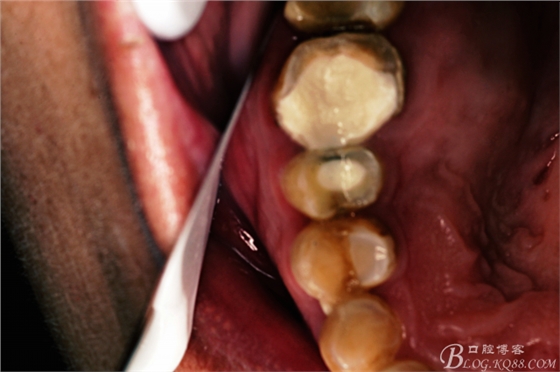

圖1.術(shù)前患者的口內(nèi)照片:15、16頰側(cè)黏膜膨隆、捫診有乒乓感